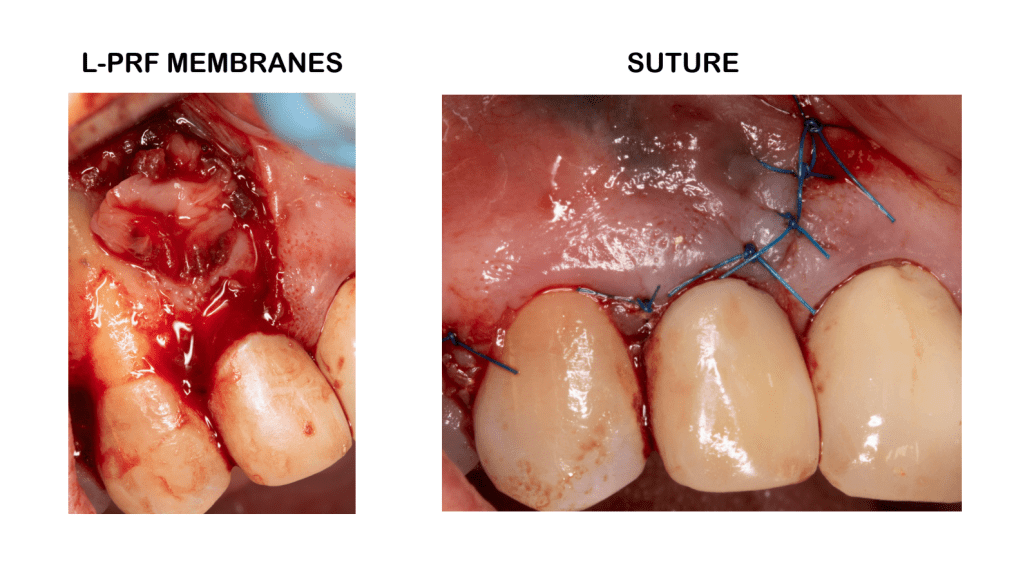

Reabsorción externa, tratamiento quirúrgico